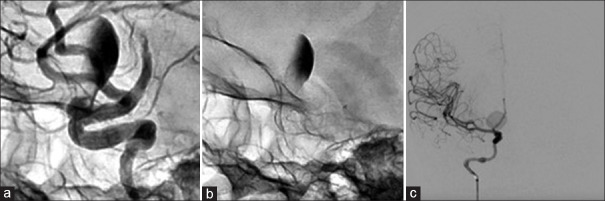

血流分流支架越来越多地用于颅内动脉瘤的治疗,特别是当存在不利于线圈栓塞的因素时,如颈部宽和动脉瘤尺寸大。然而,它的使用并不能保证成功,特别是在巨大病变中,未能获得动脉瘤闭塞会导致动脉瘤壁长期不稳定,导致动脉瘤生长和晚期破裂。我们提出的情况下,65岁的妇女谁遭受晚期动脉瘤扩张和破裂,2年零4个月后,分流治疗巨大的眼段动脉瘤。虽然尚未完全了解,但这种现象的病理生理学有一个必要因素:不完全的动脉瘤闭塞。当出现这种情况时,主要有两个因素:支架置入后囊内血流的增加以及部分血栓形成和支架本身的存在引起的局部炎症。为了防止这种并发症,必须确保动脉瘤完全闭塞,并鼓励使用联合技术。

Flow-diverting stents have been increasingly utilized for the treatment of intracranial aneurysms, especially when there are factors that go against coil embolization, such as wide neck and large aneurysm size. However, its use does not guarantee success, especially in giant lesions, and failure to obtain aneurysmal obliteration can result in long-term instability of the aneurysmal wall, leading to aneurysmal growth and late rupture. We present the case of a 65-year-old woman who suffered from a late aneurysmal dilation and rupture, 2 years and 4 months after flow-diverting treatment of a giant ophthalmic segment aneurysm. Although not fully understood, the pathophysiology of this phenomenon has one necessary factor: incomplete aneurysmal obliteration. When this scenario is present, two main factors take place: the augmentation of intrasaccular blood flow after stent delivery and the local inflammation caused by partial thrombus formation and the presence of the stent itself. To prevent this complication, complete aneurysmal obliteration must be assured, and the use of combined techniques is encouraged.